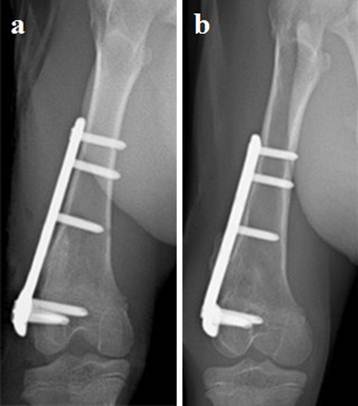

Radiographic analysis of the femurs in the goats revealed that the sliding plate group could be extended as the femur grew. The epiphyseal morphology in the sliding plate group was kept essential normal. However, the phenomenon of the epiphyseal growth retardation and premature closure were very common in the regular plate group (Fig. 2 and Fig. 3).

Fig 3

Experimental goat distal femur was fixed with regular plate. The plate and screws restricted the epiphyseal unequal growth. a: Posterior-anterior radiograph of goat femur (postoperative 0 day). b: Posterior-anterior radiograph of goat femur (postoperative 4 weeks).